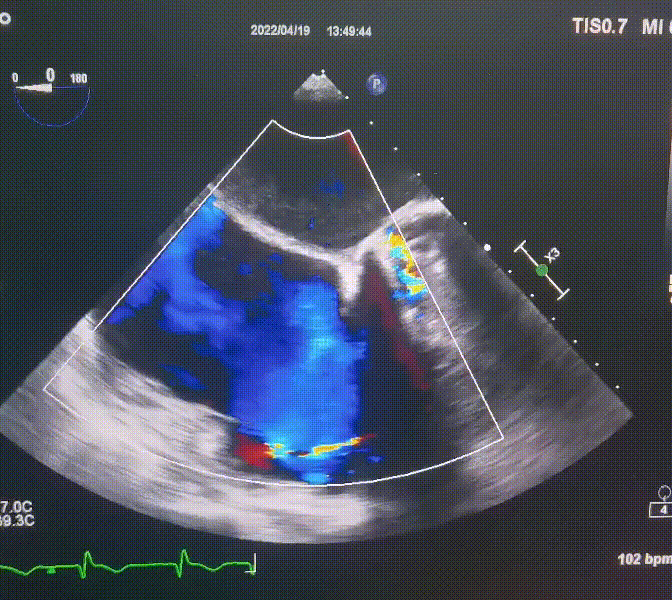

術(shù)前超聲提示:

1.右心、左房明顯增大;

2.二尖瓣人工機械瓣功能正常,無瓣周漏;

3.三尖瓣環(huán)巨大擴張,收縮期瓣葉對合不攏,收縮期三尖瓣房側(cè)見大量反流信號,反流面積15-20cm²,TRVmax:240cm/s,跨瓣壓差:23 mmHg。

圖1.術(shù)前超聲